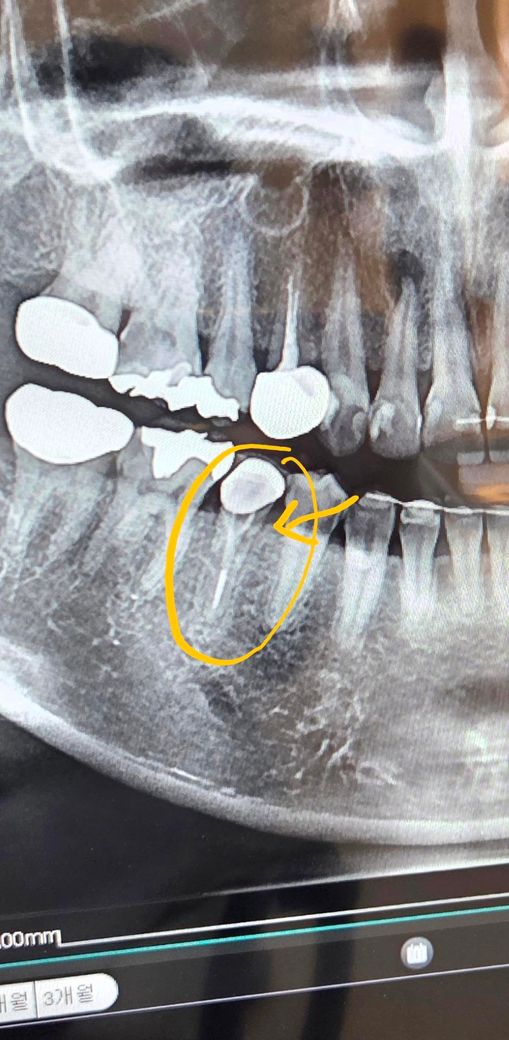

예전에 신경치료 했던 곳인데...

엑스레이를 찍어보니 하얀색 선도 없어지고

그 사이에 검은 색? 같이 뭐가 생겼네요...

치아 잇몸쪽에서 염증이 튀어나오고 있어요...

재신경치료하면 살릴 수 있을까요?

아님 무조건 임플란트인가요ㅠㅠ??

농양이 잡혀 고름이 나온다는 말같네요 재신경치료 내지는 치근단 절제술이 필요할 것 같고 발치도 염두해두어야겠습니다